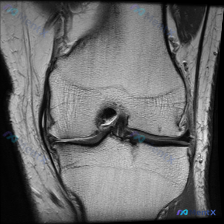

刚整理了一个有意思的读片病例,临床和影像表现有点冲突,分享一下完整分析思路: 病例基础信息 这是一张膝关节MRI冠状位T1加权成像(T1WI),用户提示观察内容为「软骨异常」。 影像读片结果 先给大家说清楚各个结构的观察情况: 1. 骨骼结构:股骨远端、胫骨近端显示清晰,骨皮质低信号、骨髓腔中等信号...

看到这个病例很有代表性,整理了完整资料和分析思路分享给大家 病例与影像资料 本次评估的是单张膝关节MRI T1加权序列冠状位图像,临床提出问题:影像是否存在软骨异常? 对影像的详细评估结果如下: 1. 骨骼系统:股骨远端、胫骨近端骨皮质连续,无骨折,骨髓信号正常,无局灶低信号,无骨质破坏、囊变或骨赘...